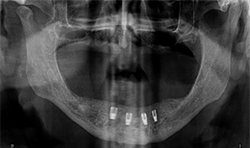

A 71-year-old male presented with a full maxillary denture and retained lower left canine and lower right first premolar (Fig. 3). He desired a semi-permanent solution to improve fit, function of upper and replace all missing teeth on the lower. An initial panoramic radiograph was taken for surgical and restorative planning purposes. The patient and doctor discussed options and it was decided  a new maxillary full denture and a fixed hybrid prosthesis on the lower arch would be acceptable treatment options.

Fig.3